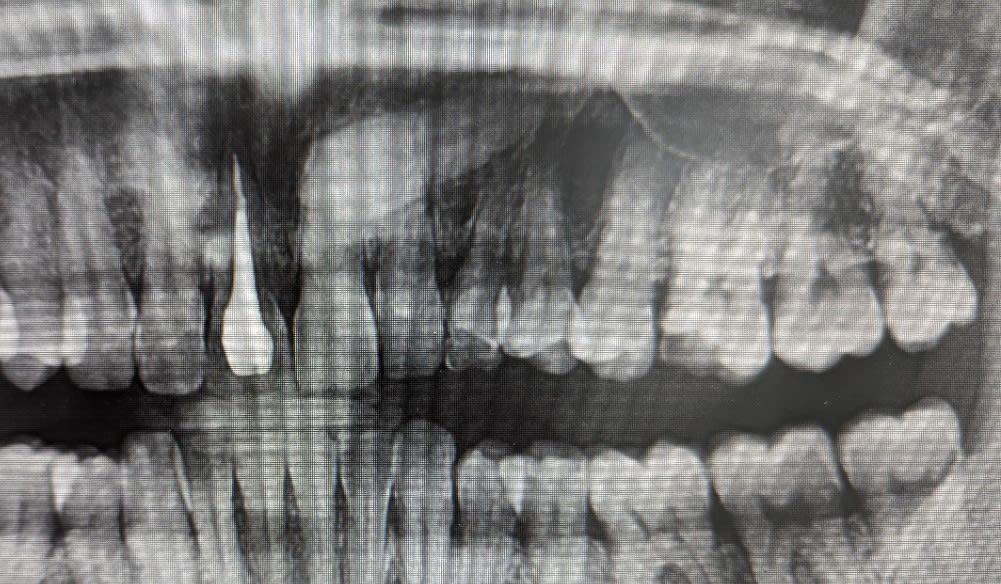

patiente dont la canine de lait 63 est devenue mobile ( je me demande s il n y a pas une fracture au niveau de la racine) et la canine incluse couchée à 90 degré occupe tout le volume osseux de la corticale externe à la corticale interne sous la 63. l option bridge collé pour remplacer la dent ne me parait pas trop viable dans le temps.

quelqun a déja posé un implant dans une canine incluse? il y a un protocole particulier? je vais forcement toucher le nerf de la canine et je ne vois pas trop comment ça peut aller correctement.

sinon je crains que l extraction de la canine incluse soit extrêmement délabrante et traumatisante même si c est l option qui semble la plus sage.

Image de la canine plus grosse = position palatine à 100%

Elle se situe juste derrière les incisives

La seule difficulté, décoller la muqueuse palatine….

Après quand on voit cette coupe cbct, je ne suis pas certain que l’extraction soit une partie de plaisir.

sur les autres coupes la couronne est en palatin et l apex en vestibulaire, la dent occupe vraiment une grosse partie du volume osseux de de la crête .